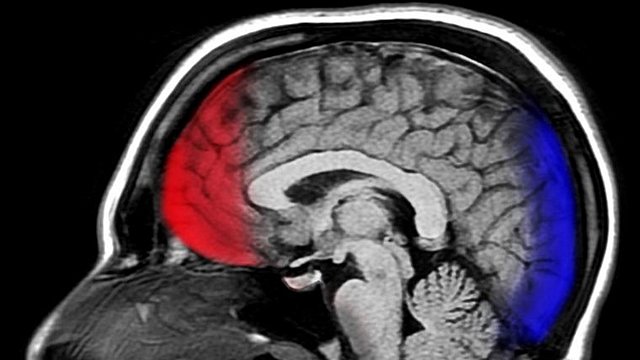

La parte importante de su obra se refiere a la organización evolutiva del sistema nervioso, para el que propuso tres niveles: un nivel inferior, un nivel medio, y un nivel superior. En el nivel inferior, los movimientos se representarían en su forma menos compleja; estos centros se encontrarían en la médula espinal. El nivel medio consistiría en la llamada área motora de la corteza, y los niveles motores superiores se localizarían en el área prefrontal.

Las mismas áreas, al estar lesionadas, causaban la pérdida de las funciones que se obtenían mediante la estimulación. Ferrier también fue capaz de demostrar que la estimulación de alta intensidad de las áreas corticales motoras provocaban movimientos repetitivos en el cuello, la cara y los miembros, que evocaban considerablemente los ataques epilépticos observados por neurólogos en seres humanos y animales.

Las lesiones extensas basales mediales pueden producir un cuadro consistente en desinhibición, falta de control emocional, risa fácil, inadecuación social, obsesiones, falta de responsabilidad, distractibilidad, infantilismo, hiperactividad e hiperreactividad. La amnesia postraumática es muy frecuente en los TCE graves y moderados, así como los déficits permanentes de memoria, sobre todo si existe hemorragia o hipoxia.